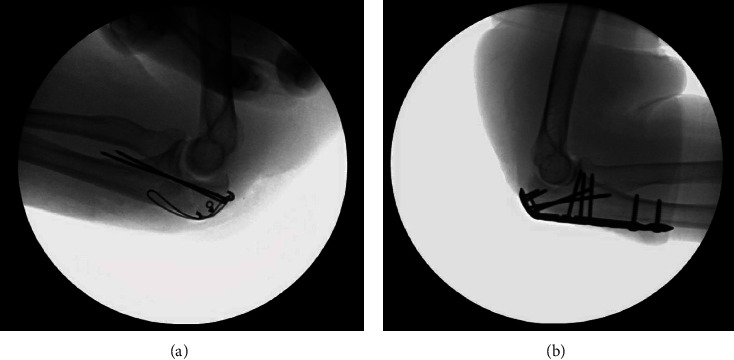

Abstract Image